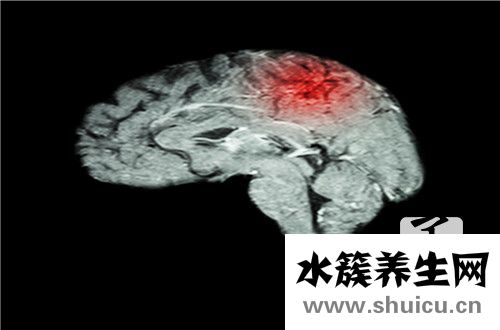

腦外科手術是一種危險的重大外科手術治療。 手術前必須做一些準備工作以清除腦積水。 通常,使用一些藥物或引流方法清除腦積水,兩周后即可清除。 更嚴重的患者大概需要二十天。 手術后,要注意患者的...